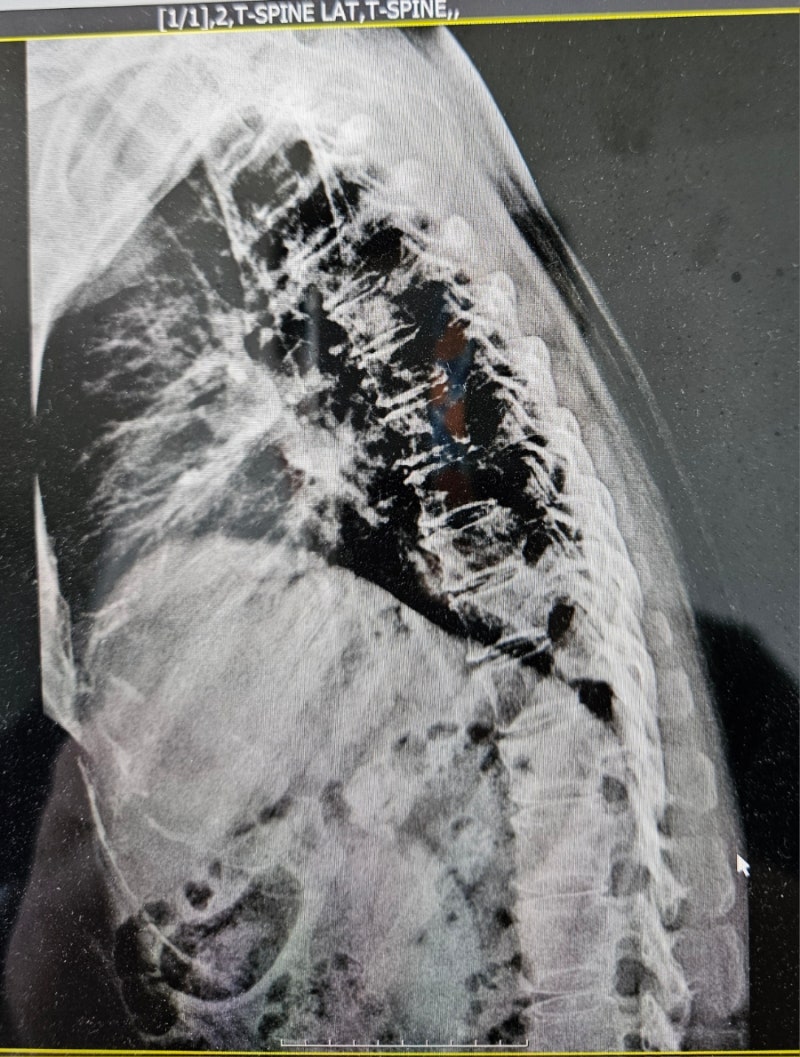

촬영부위: 흉추 (Thoracic Spine)

촬영방향: AP 및 LAT (정면 및 측면)

흉추 12번(T12) 압박골절 확인됨

척추체 전방의 함몰, 쐐기형 변형(wedge deformity) 관찰해당 부위 국소 후만 변형 유발

2. Cobb Angle (후만각) 측정 결과

T11–L1 기준 Cobb angle: 약 28도 ±2도

이는 정상 상한선을 초과함

T11–L1 정상 후만각은 0도에서 10도 사이로 알려져 있음

(정상 범위 최대 15도, 평균은 약 5도 전후)

해당 환자의 연령대(56세 여성)를 고려해도 이 구간에서 자연 후만 20도 이상은 드물며, 사고 전에는 비교적 정렬이 유지되었을 가능성이 높음

56세 여성 환자의 흉추 12번 부위 압박골절에 따른 구조적 변형이 영상에서 확인됩니다. Cobb angle(T11–L1)은 약 28도이며, 이는 정상 상한선(15도)을 초과하고, 사고 전 정렬이 정상(0~10도)이었다면 최소 15도 이상의 후만각 증가로 판단됩니다.